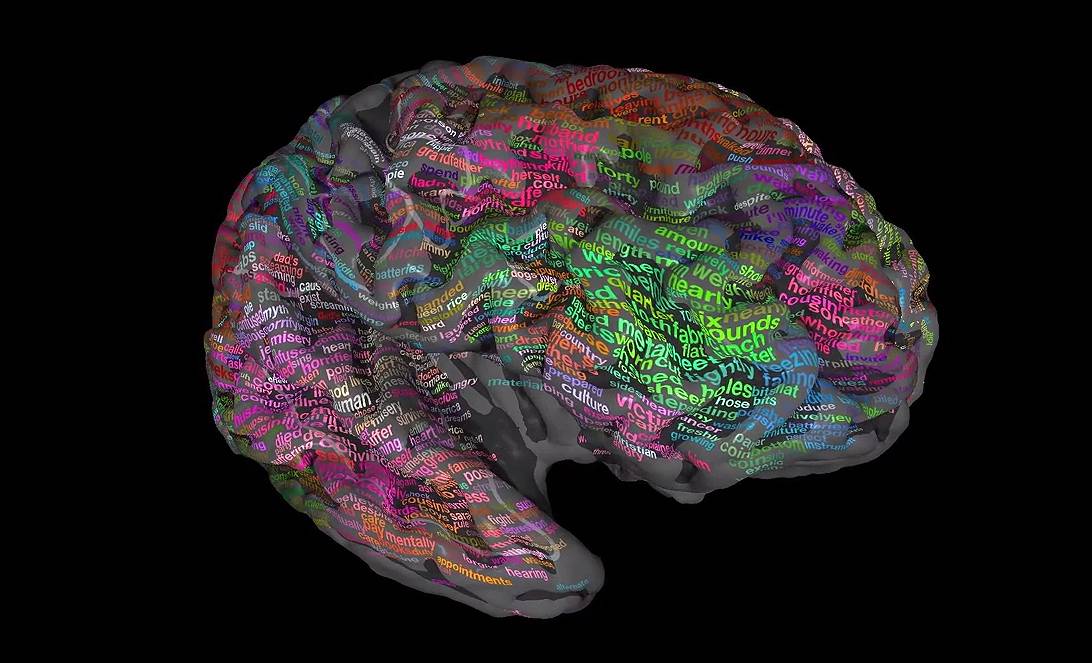

📊 Visualización Gráfica 1: Conectividad Estructural Humana (Tractografía)

Enseguida, se exhibe una visualización creada por técnicas avanzadas de DTI, ilustrando la compleja arquitectura de la materia blanca cerebral humana.

¡Observa! Es una imagen en alta fidelidad, mostrando la tractografía, detallando las vías de comunicación más importantes entre y dentro de los hemisferios cerebrales.

Mapa del Cerebro Humano, en tractografía. Esta imagen, creada con Tensor de Difusión (DTI), ilustra la compleja conexión estructural (la materia blanca, ¿sabes?). Los colores revelan la dirección de los tractos axonales: rojo, para la comunicación izquierda-derecha (como el cuerpo calloso), verde para adelante-atrás y azul para arriba-abajo. Este «cableado» es la base física donde actúan las redes funcionales.